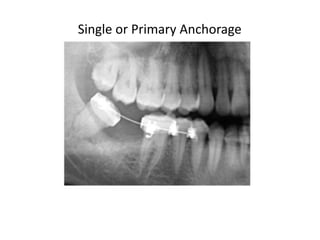

According to the document, there are two main ways to classify orthodontic anchorage: 1) According to the site of anchorage which includes intraoral, extraoral, and muscular anchorage. 2) According to the number of anchorage units which includes single or primary, compound, and reinforced anchorage. The document discusses different types of orthodontic anchorage classifications.